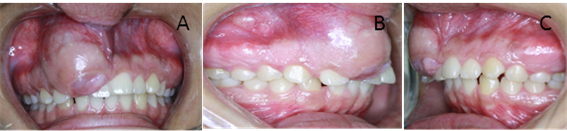

Figura 3. Imágenes Intrabucales

Imagen (a) frente (b) perfil derecho (c) perfil izquierdo.

Figura 4.  Intrabucales Imágenes.

Imagen (a) Oclusal superior (b) oclusal inferior (c) perfil oclusal

Las fotografías intrabucales son de gran ayuda para el diagnóstico de patologías en los pacientes, son una herramienta útil y adicional que aporta información valiosa para el profesional de la odontología, aporta registros clínicos, en este caso la cirugía bucal.